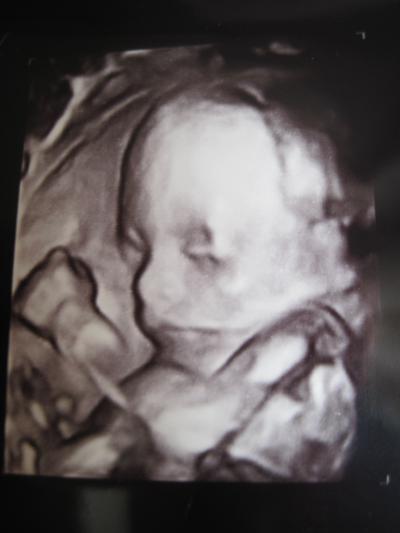

Hallo Mädels, auch ich war ja gestern zur FD und war im Wartezimmer dann total nervös (hab ja selbst ne 3.Niere und bekomme Medis wegen dem Asthma) und es wurde auch nicht besser weil ich 1h warten mußte trotz Termin. Der Doc war aber ganz nett nur konnte er nicht fassen das ich in der 21. Woche sein soll - hab ja nur nen Mini-Bauch den man kaum sieht und das obwohl ich ganz klein und sehr schlank bin. Irgendwann meinte er dann auch ich hätte wirklich nur Baby im Bauch und nicht mal die "kleinste Fettschicht" - obs nun nen Kompliment war oder nicht KEINE AHNUNG... Er hat dann angefangen zu schallen und nach 2min gesagt es wird ein Mädchen er sieht keinen Schnippi und würde mir dann später auch die Gebärmutter der Kleinen zeigen. (hat er dann auch also Verwechslung ausgeschlossen ) Bei unser großen war dann abends voll Drama angesagt weil sie NUR nen Jungen wollte - SIE sei schließlich die einzige Prinzessin. Haben ihr dann lang und breit erklärt das wir sie ja nicht weniger lieb haben nur weil da noch nen Mädchen kommt. Der Große hat sich allerdings riesig gefreut (dabei dachte ich er sei total geknickt wenns nen Mädchen wird) und konnte sich gar nicht wieder einkriegen. Bei unser Prinzessin stellt sich die Freude hoffentlich auch noch ein. Und dann können wir uns alle aufs Mädchen freuen. Der Doc hat dann eine Stunde geschallt und es sah auch alles echt gut aus. Hat sogar auf 4D umgeschalten und uns nen schönes Bild vom Gesicht gemacht. mein Schatz konnte es zu hause gar nicht fassen das man die Kleine schon richtig erkennen kann. Bisher wollte er immer nicht mit weil er meint er kann da eh nix erkennen und selbst wenn der Doc ihm 100% erklärt was es sein soll. Tja gestern abend war er etwas wehmütig das er nicht mit war. (hatte aber auch noch nen 3D /4D US gesehen) Dann hat die Schwester den Bericht für meinen FA fertig gemacht und meint zum Doc er müssen noch nach der Plazenta schauen. Tja und da kam die Überraschung ich habe eine Plazenta bipartita - so zu sagen 2 Plazentas mit freilaufenden Gefäßen in der Eihaut. Beide Teile sind gleich groß nur liegt eins an der Vorderwand und eins an der Hinterwand. Und wenn ich das richtig verstanden habe läuft auch die Nabelschur ein Stück in der Eihaut. Für die Schwangerschaft macht das wohl nichts ABER unter der Geburt ist das wohl nicht ohne. Besonders bei nem Blasensprung weil man ja nicht weiß wo der ist und wenn er genau an der Stelle ist wo die beiden Teile verbunden sind hat das Baby wohl keine Chance. DIE Nachricht war echt heftig. Zumal ich beim großen nen Blasensprung in der 35SSW hatte. Ach ja und sollte ich auch nur das kleinste Anzeichen einer Blutung haben muss ich SOFORT ins Krankenhaus. Und ich muss mich jetzt in der 24.SSW in der Entbindungsklinik vorstellen damit die wissen worauf die sich "einlassen" wenn ich zur Entbindung komme und halt beide Plazentateile nach der Geburt raus müssen... Hatte das schon mal eine von euch oder kann mir von irgendwelchen Erfahrungen berichten? Bild vom US hab ich angehängt - und jetzt freuen wir uns erst mal auf die 2.te Prinzessin... LG Isa mit Prinzessin (309g u. 21cm)

Bild zu Bericht FD von gestern + Outing + 4D Bild + leider nicht alles ok :-( - Forum für September - Mamis

Ohhh wie schön dass soweit alles gut ist und herzlichen Glückwunsch zum Mädel! Das Bild ist richtig gut geworden finde ich! Meine beiden Bilder sind leider nicht soooo schön, aber ein bisschen was erkennen kann man trotzdem. Stell die später mal hier ein... Fein, ich freu mich für Dich! Mach Dich wegen der Plazenta nicht allzu verrückt! Das wird schon alles gut gehen! Kenn das leider gar nicht, hab auch noch nie davon gehört... Lieeeebe Grüße, Nathalie mit Matti & Malina